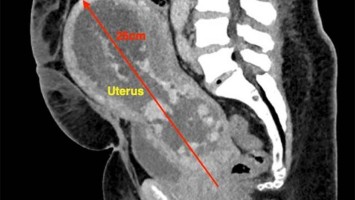

Akuter Harnverhalt in der Frühschwangerschaft

Eine 41-jährige III-Gravida I‑Para – Zustand nach Sectio – stellt sich mit Unterbauchschmerzen und tropfenweiser Harninkontinenz in der 11. Schwangerschaftswoche vor. Es besteht keine vaginale Blutung, gastroenterologische Ursachen sind ausgeschlossen. Was war der Grund für die Beschwerden?